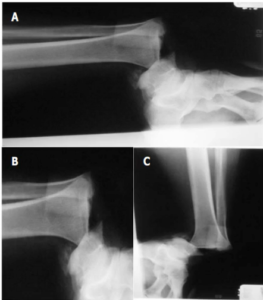

At the Comprehensive Foot and Ankle Institute we specialize in Diabetic Limb Salvage. We use very minimal to no incisions to apply a multiplanar external fixator. This device is able to hold and restore the fracture components. This is done without making any incisions.

The x-ray (above) on the right shows anatomical alignment of the severe fibular fracture, tibial fracture and ankle dislocation.

Final x-rays after the removal of the external fixator shows complete restoration of the severe ankle fracture dislocation in the diabetic patient. The patient was able to ambulate without any difficulties without any recurrences. Throughout the incidence of the surgical procedure and postoperative follow-up there was no signs of any infection.